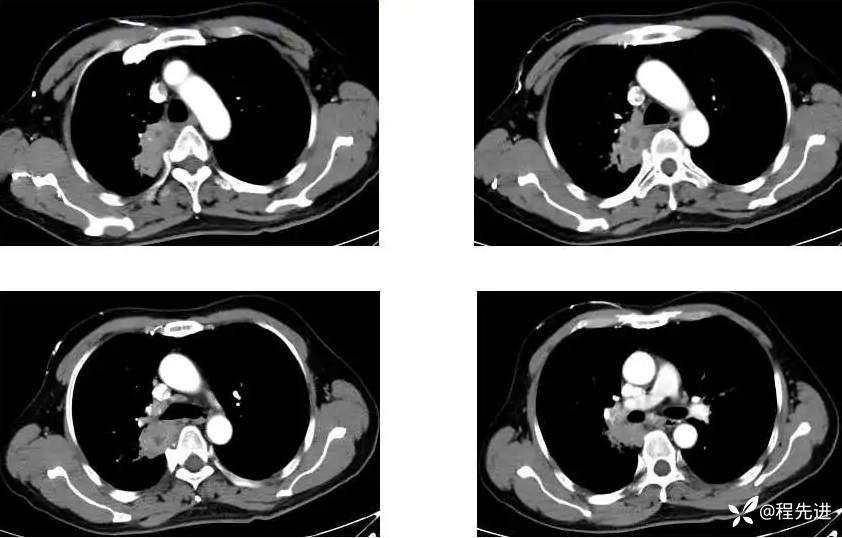

主 诉:间断咳嗽、痰中带血1月,发现肺门占位8天

现病史:患者1月前受凉后出现咳嗽咳痰,痰中见血丝,量少,伴有右侧胸痛不适,夜间有盗汗,无发热,在社区予以抗感染治疗3天(具体用药不详),胸痛症状缓解,但仍间断出现痰中带血,未再行诊治;8天前检查发现肺门占位;患者近2日咯血量较前增多,每日约4-5口,为鲜红色

CT增强: